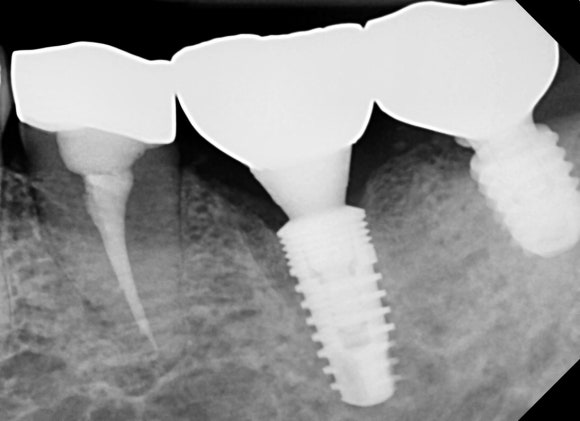

20241031

임플란트를 식립했습니다.

아직은 뿌리만 있습니다.

임플란트의 방향과 위치도 안정적입니다.